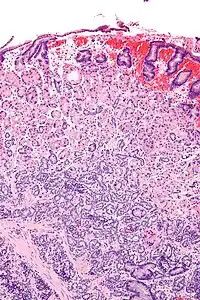

| Micrograph of a neuroendocrine tumour of the stomach. H&E stain. | |